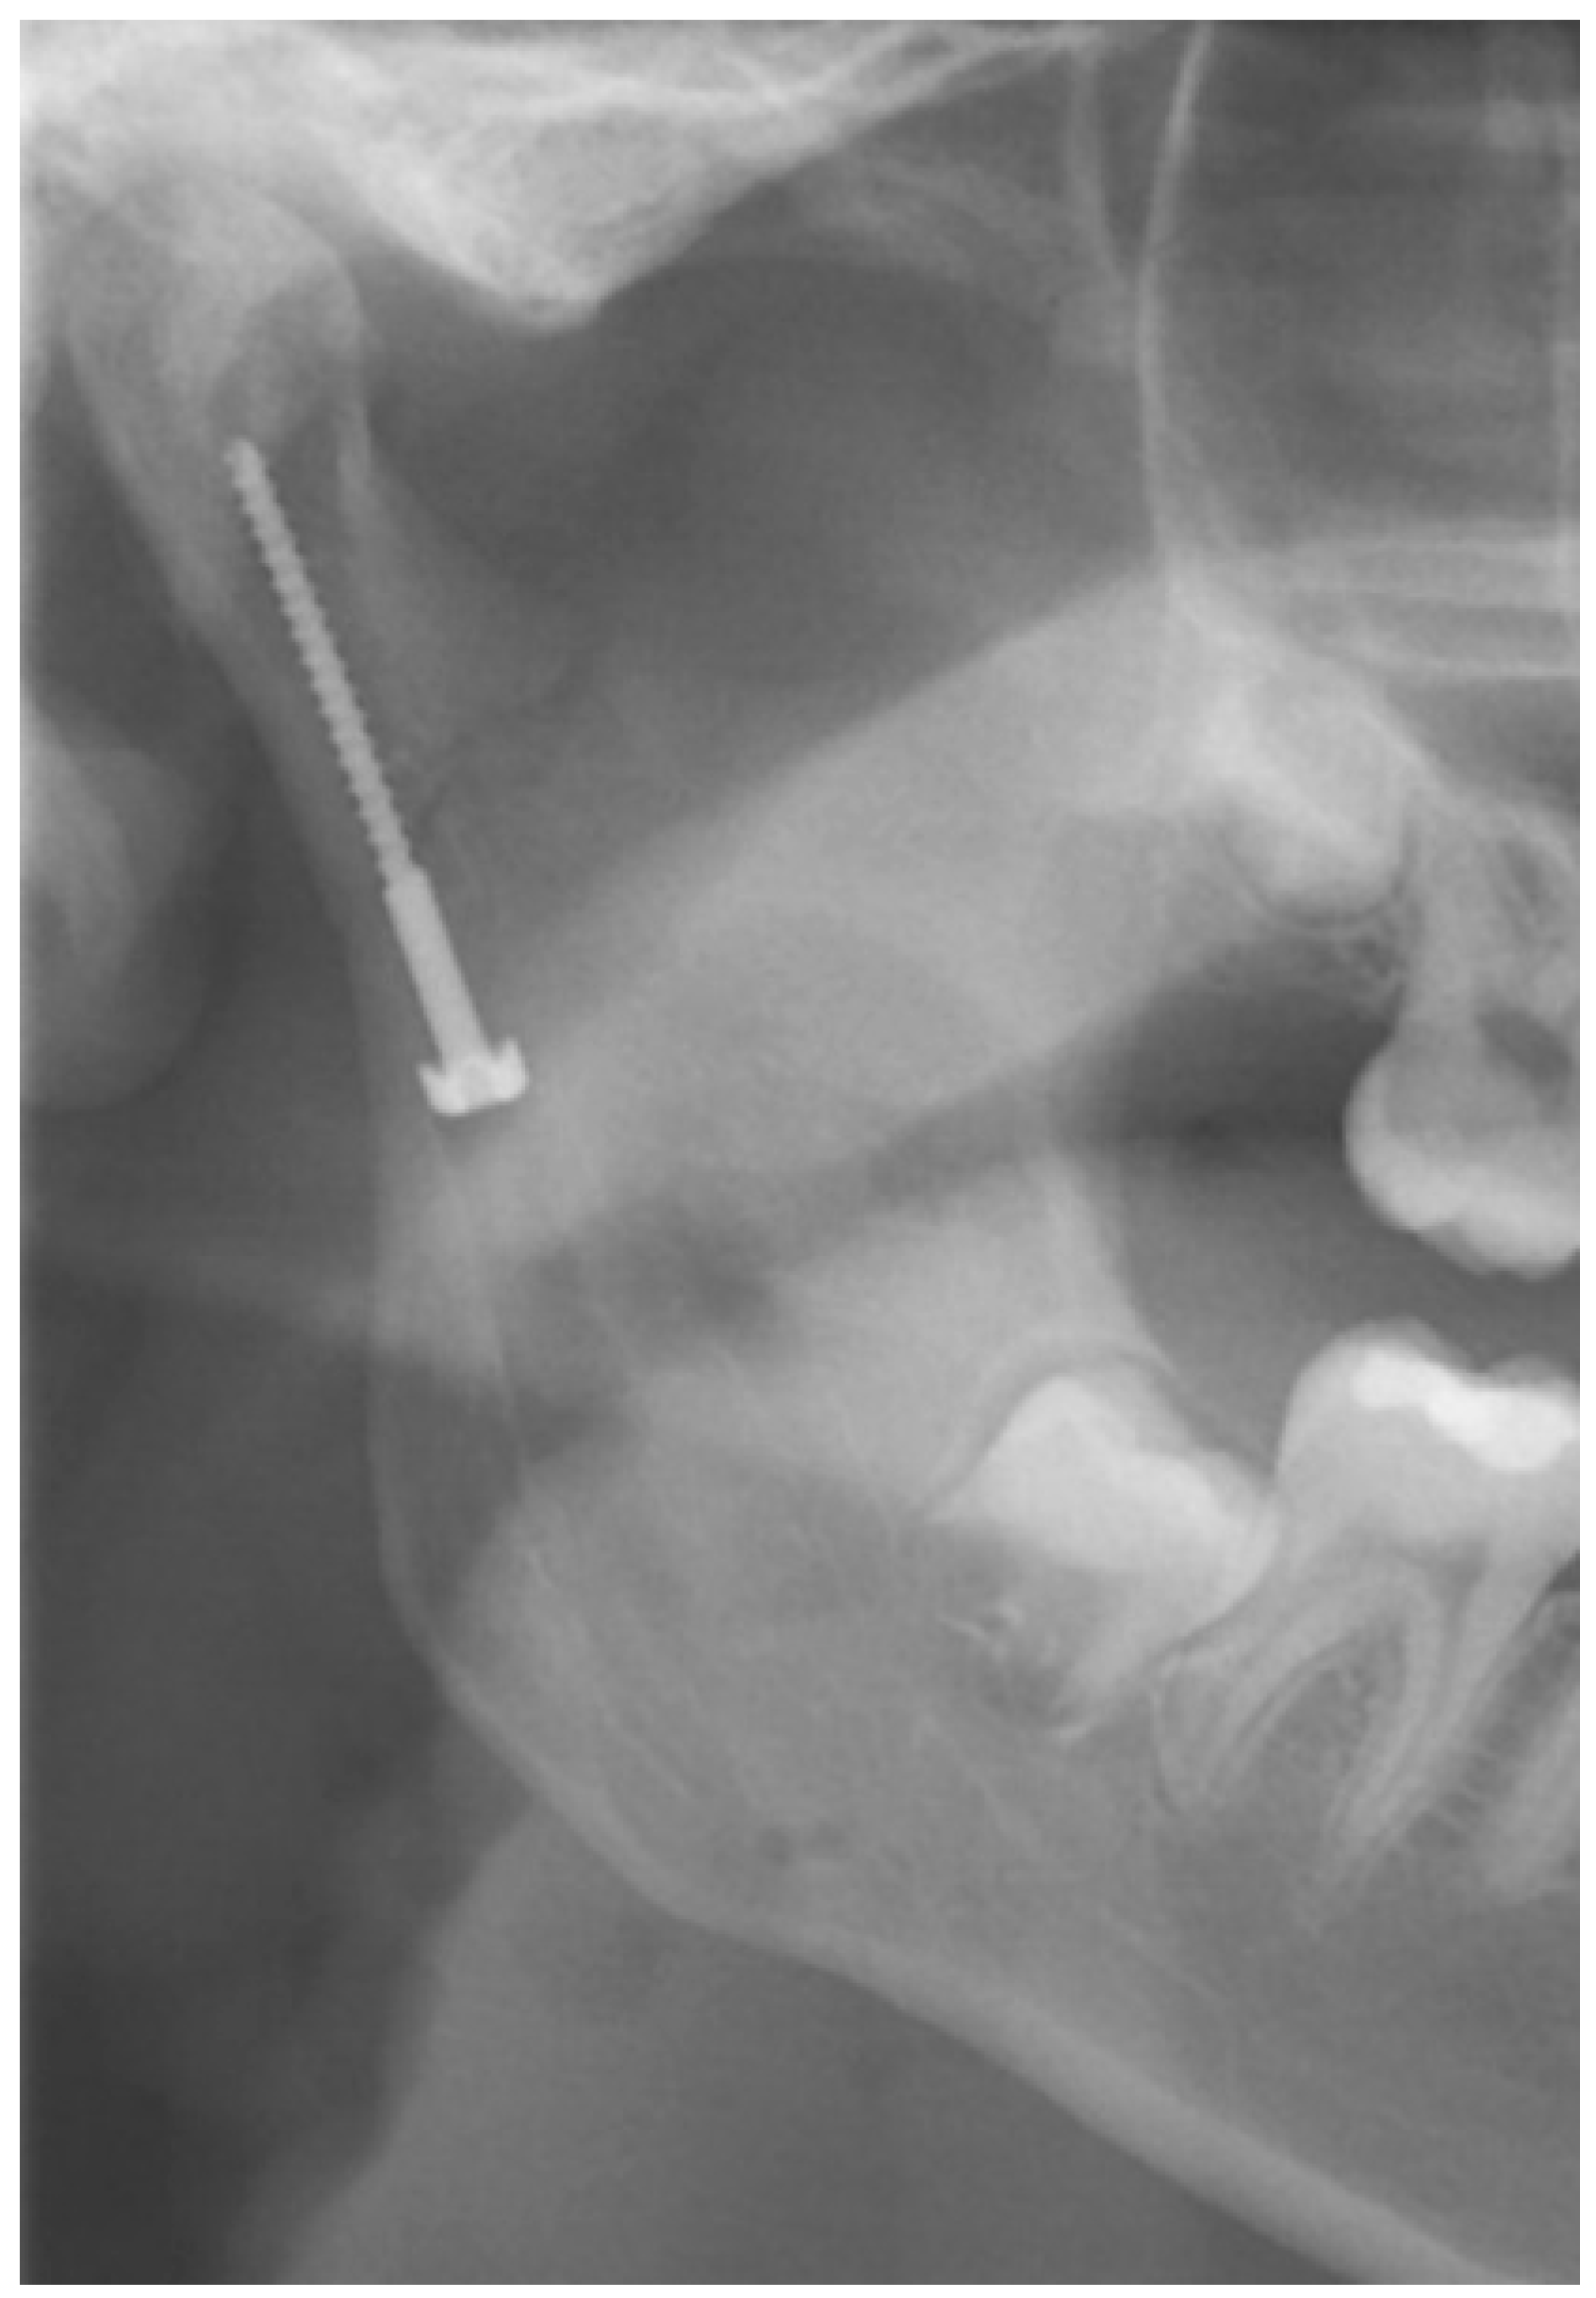

The “classic” submandibular incision, at least 2 cm caudal to the mandible’s lower border, was used for positioning a lag screw, initially described by Eckelt. Krenkel subsequently modified the Eckelt screw, adding a biconcave “washer” for force distribution (Figure 2). After dissection and reduction in the condylar fracture, a channel was drilled on the surface of the posterior border of the ramus ending at the subcondylar area. Starting from this point, the tunnel for the lag screw was drilled in the usual way. Then, the lag screw was placed, engaging the condylar process and thereby fixating the proximal fragment [20,21,22]. Krenkel’s lag screw is no longer available on the market and is of historical interest only.

Figure 2. The image shows a Krenkel’s lag screw in one of the patients treated at the authors’ department.